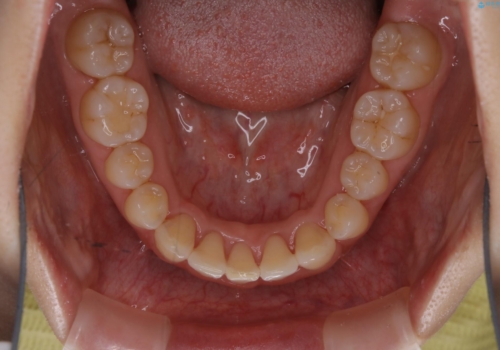

前歯のがたつきを無くすためには、スペースを確保する必要があります。上の前歯のがたつきは軽度ながたつきのため、歯と歯の間を研磨をして、そのスペースを使い並べていきます。下の前歯は、1本前歯を抜いて研磨せずに、その抜歯したスペースを使い並べることになりました。

下の前歯は、スリーインサイザー仕上げと言って、通常前歯は4本ありますが(犬歯はいれていない)、そのどれか1本を抜歯して前歯を3本にして矯正治療を行うことを言います。また、先天的に歯の本数が少ない方もいますので、矯正治療を行っていなくても元々スリーインサイザーの方もいます。